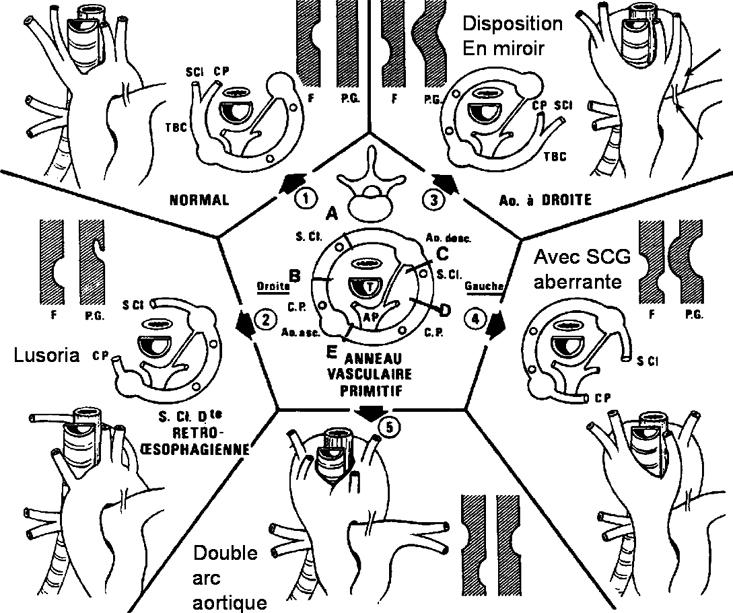

L’atteinte cardiaque peut se faire par propagation de voisinage en cas de tumeurs bronchiques ou médiastinales (A), par voie hématogène en cas de métastases à distance (cf: métastase intra-myocardique d’un cancer ORL illustrée en B), par voie lymphatique ou veineuse prenant les cavités cardiaques droites comme dans les exemples ci-dessous d’extension d’un EOA utérin enclavée dans l’infundibulum (C) ou de tumeur de Grawitz envahissant l’oreillette droite (D).